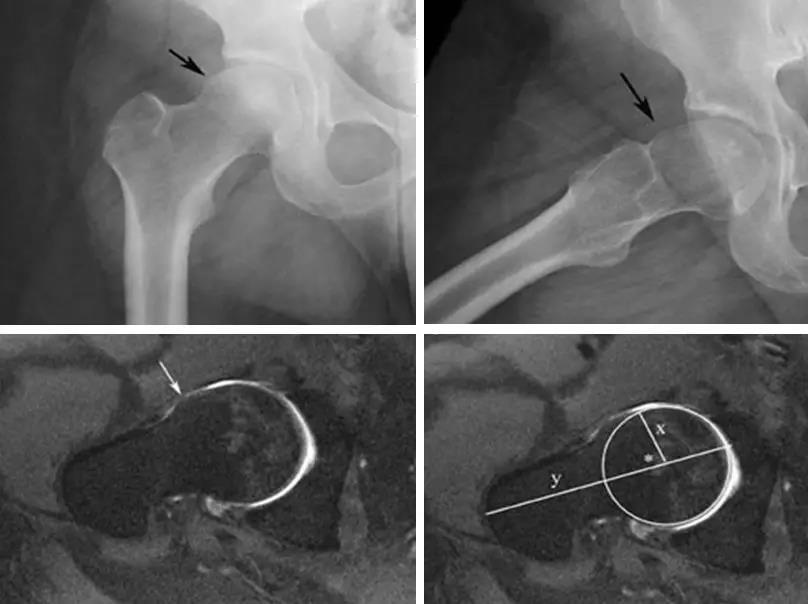

- 股骨头中心O点为圆心,股骨头正常最大半径为r,从股骨头颈连接处骨质与这个圆的交点(A点)到股骨头中心点作直线OA,此直线与股骨颈中轴线OB的交角为α角。

- 反映股骨颈骨赘突出程度,α角越大,越容易发生前上方股骨头颈与髋臼唇的撞击。

- FAI组中该角平均为74.0°±5.4°,正常对照组为42.0°±2.2°。

- α角>50°是诊断FAI的临界值。